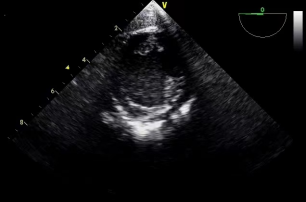

3.经胃底部(图6):距门齿50cm,左室乳头肌短轴观、二尖瓣短轴观、经胃底左室长轴观、经胃底右室流入道观等。

胃底 左室乳头肌短轴(图6)